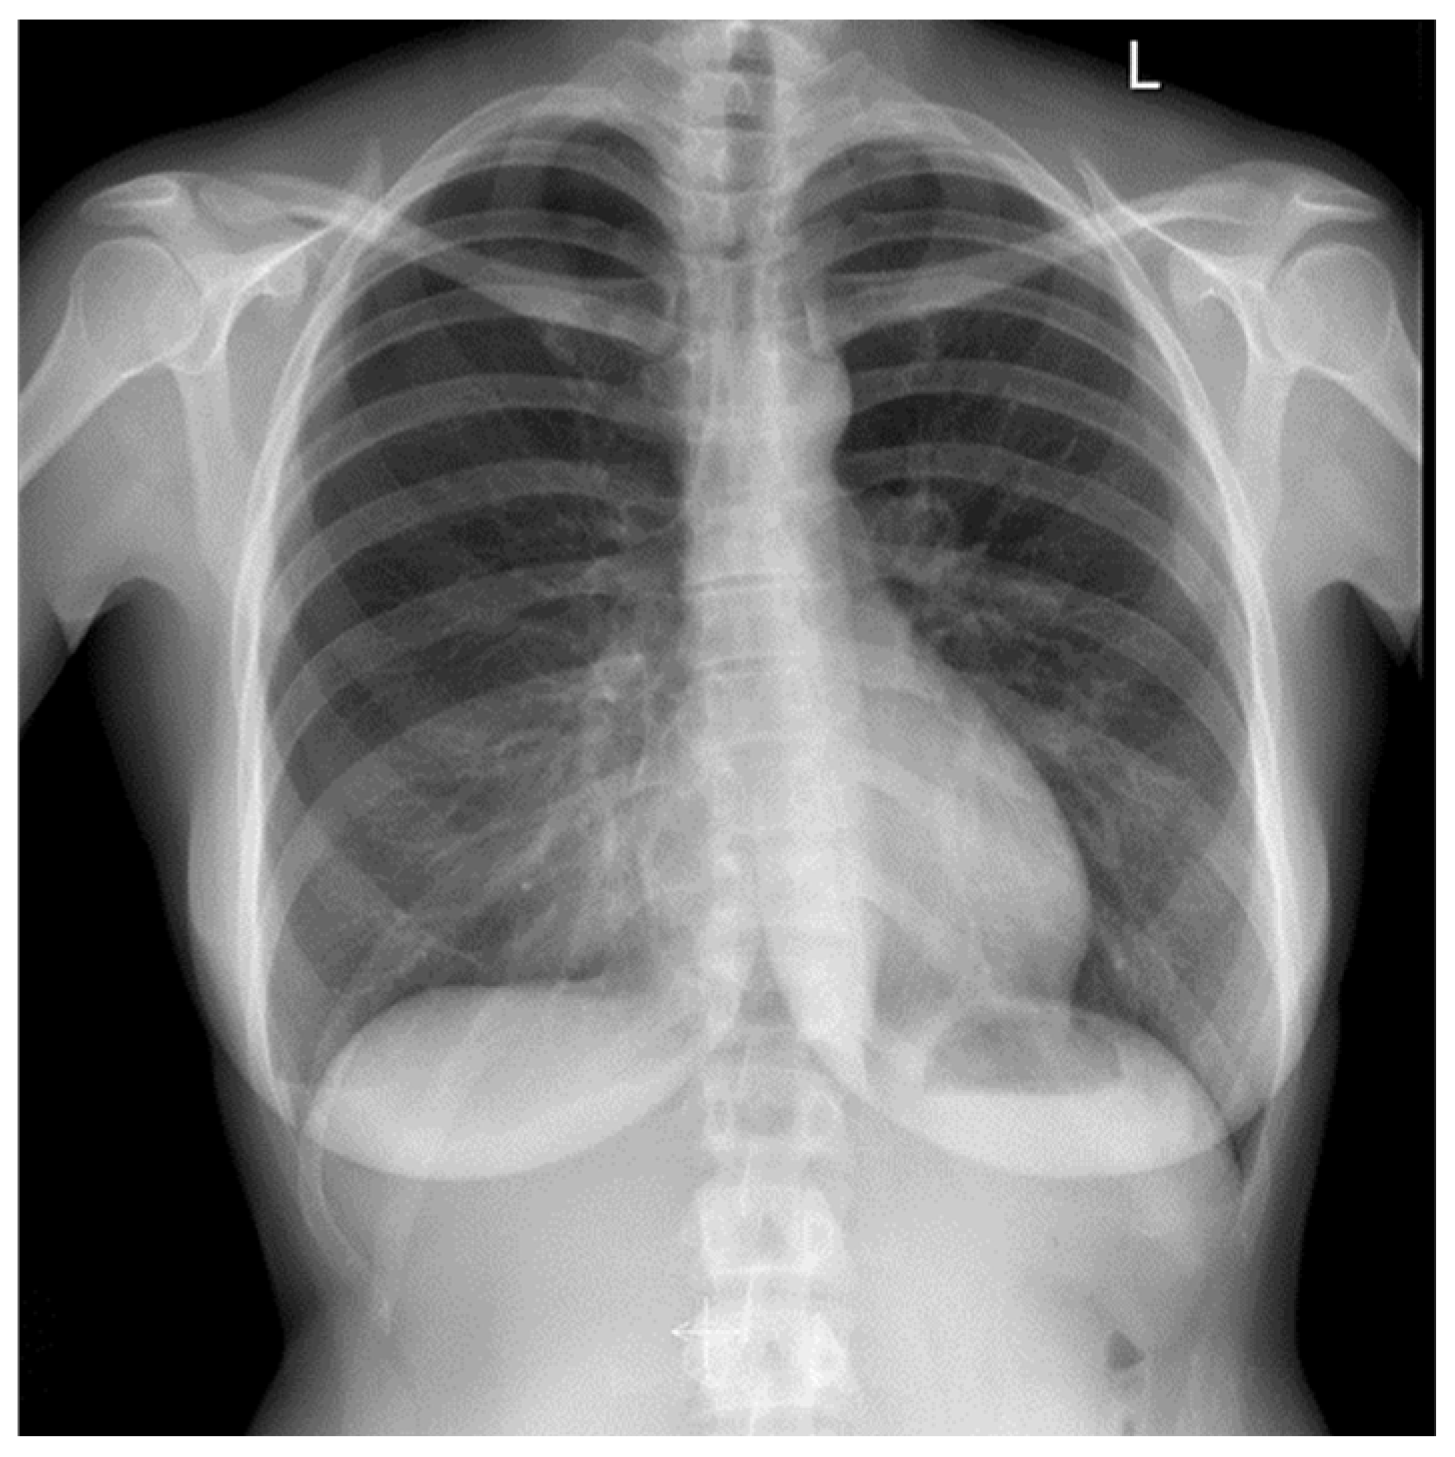

2.2. Clinical Findings

2.4. Diagnostic Assessment and Therapeutic Intervention